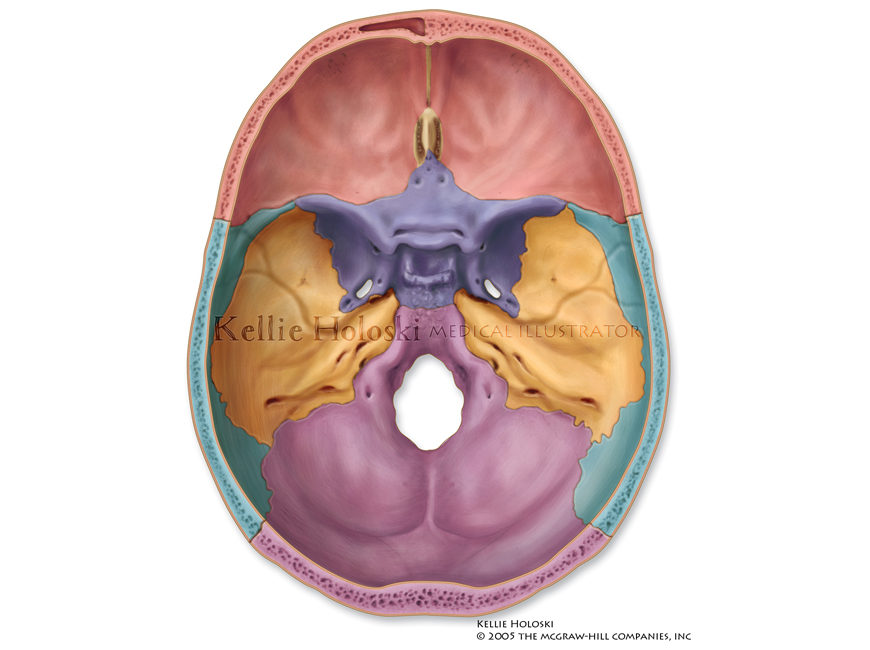

Base of Skull: Interior,

Adobe Photoshop

Published in Human Anatomy, 1st Edition by Michael McKinley, Valerie O’Loughlin;

©The McGraw-Hill Companies -